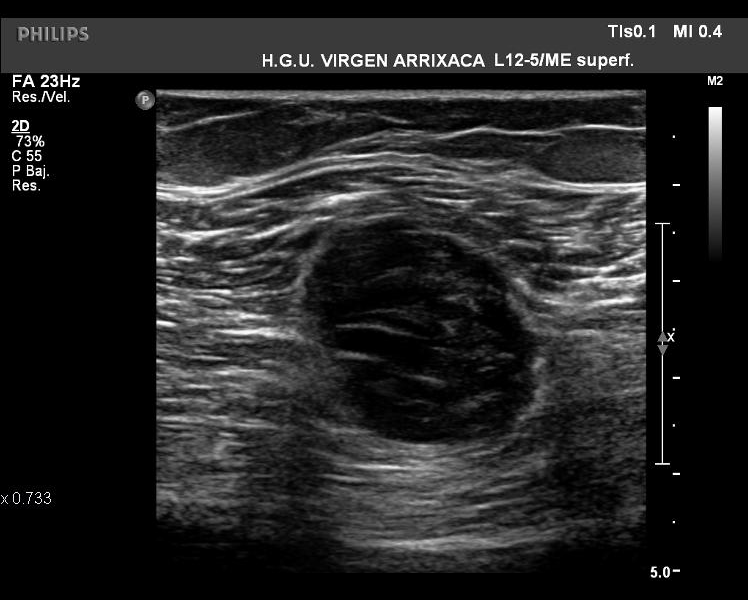

La ecografía nos permite averiguar la naturaleza de la lesión (óseo, muscular, subcutáneo…) sin aplicar radiación y de una manera relativamente sencilla.

Tras la realización de la ecografía en el muslo derecho de la paciente, obtenemos las siguientes imágenes: